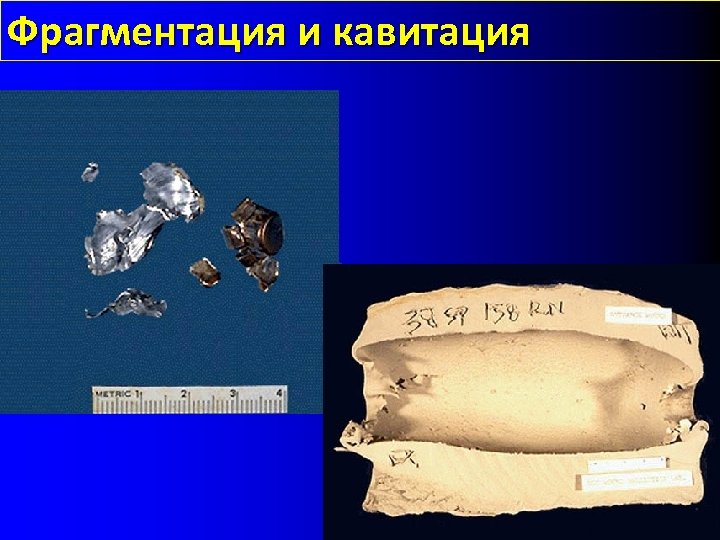

Фрагментация и кавитация

Фрагментация и кавитация

Скорость Низкая менее 1000 ft/sec, не создает кавитацию и не фрагментирует метафиз Средняя между 1000 -2000 ft/sec Высоко скоростная более 2000 -2500 образуется кавитация и ударная волна - M 16 в 3250 ft/sec

Скорость Низкая менее 1000 ft/sec, не создает кавитацию и не фрагментирует метафиз Средняя между 1000 -2000 ft/sec Высоко скоростная более 2000 -2500 образуется кавитация и ударная волна - M 16 в 3250 ft/sec